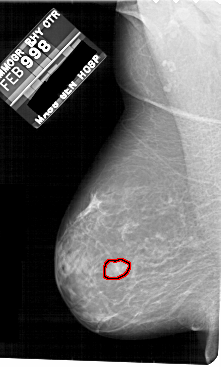

A_1811_1.LEFT_MLO

LEFT_MLO LINES 5491 PIXELS_PER_LINE 3301 BITS_PER_PIXEL 12 RESOLUTION 43.5 OVERLAY

FILE: A_1811_1.LEFT_MLO.OVERLAY

TOTAL_ABNORMALITIES 1

ABNORMALITY 1

LESION_TYPE MASS SHAPE IRREGULAR MARGINS MICROLOBULATED

ASSESSMENT 4

SUBTLETY 2

PATHOLOGY BENIGN

TOTAL_OUTLINES 1

BOUNDARY